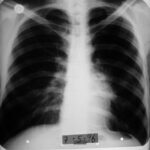

1995 - İlk Başvuru

Öksürük, ateş, sırt ağrısı - küçük hücreli anaplastik karsinom

Teşhis

Biyopsi sonucu pozitif, kemoterapiyi reddetti

6 Kasım 1995 (2 hafta sonra)

Röntgende kitle küçülmüş durumda görüldü.

1996 Mayıs (7. Ay)

Röntgen tümörün tamamen kaybolduğunu gösterdi.